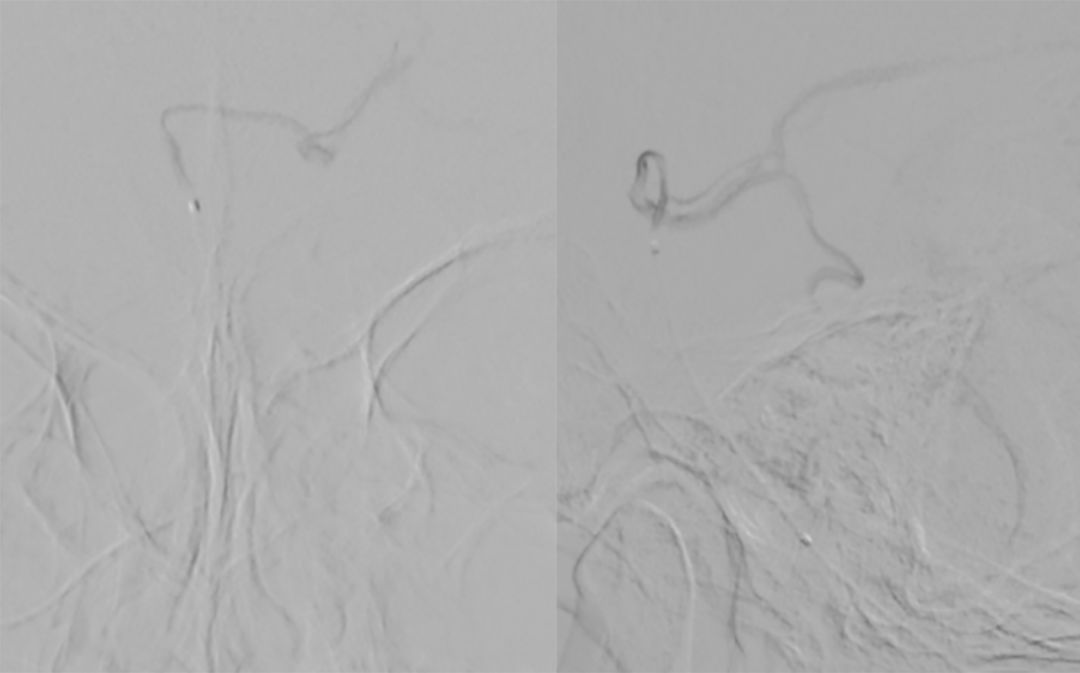

2. 将Echelon-10微导管置入基底动脉较粗的管腔中进行微量造影(正位、侧位)(图6):左侧大脑后动脉显影。

图6

3. 再将Echelon-10微导管置入基底动脉较细的管腔进行微量造影(正位、侧位)(图7):双侧大脑后动脉及左侧小脑上动脉显影,可见动脉瘤位于左侧小脑上动脉。

图7

4. 最后将Echelon-10微导管置入基底动脉中下段进行微量造影:基底动脉2个管腔、 双侧大脑后动脉显影、小脑上动脉均可显影(图8)。

图8